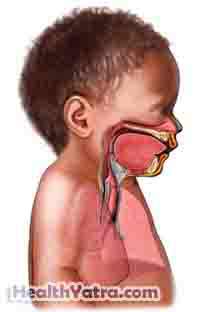

Transient Tachypnea Of Newborn Definition, Causes, Symptoms

www.healthyatra.com

www.healthyatra.com tachypnea respiratory newborn transient virus para causes syncytial infant ingles fisioterapeutas nurses system distress técnico por ards

Tachypnea respiratory newborn transient virus para causes syncytial infant ingles fisioterapeutas nurses system distress técnico por ards. Solitary fibrous tumors(sft). Small bowel cancer